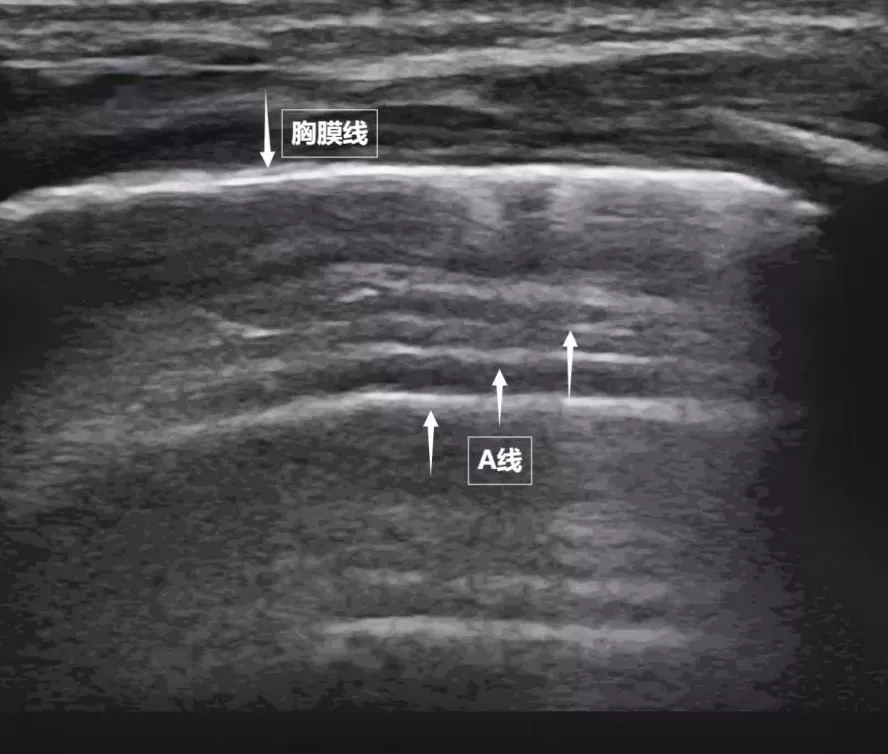

第一景:" 海岸线与海浪 " ——胸膜线与 A 线

当声波穿过胸壁肋骨缝隙,首先会遇到紧贴肺表面的光滑薄膜——壁层胸膜和脏层胸膜。两者紧密相贴,中间没有多余的气体或液体。它们在屏幕上呈现为一条明亮、光滑的水平线,共同构成了胸膜线。这条线就是肺的 " 海岸线 "。在它的下方,由于肺泡内大量气体对声波的强烈反射,会出现一系列与胸膜线平行的、等间距的、重复出现的明亮平行线,像海浪般不断向屏幕深处延伸,这就是 A 线(见下图)。A 线是正常含气肺部的典型标志。它的存在直接提示肺表面含气充足,胸膜腔内无异常积液或气体。

图为正常新生儿肺部超声表现